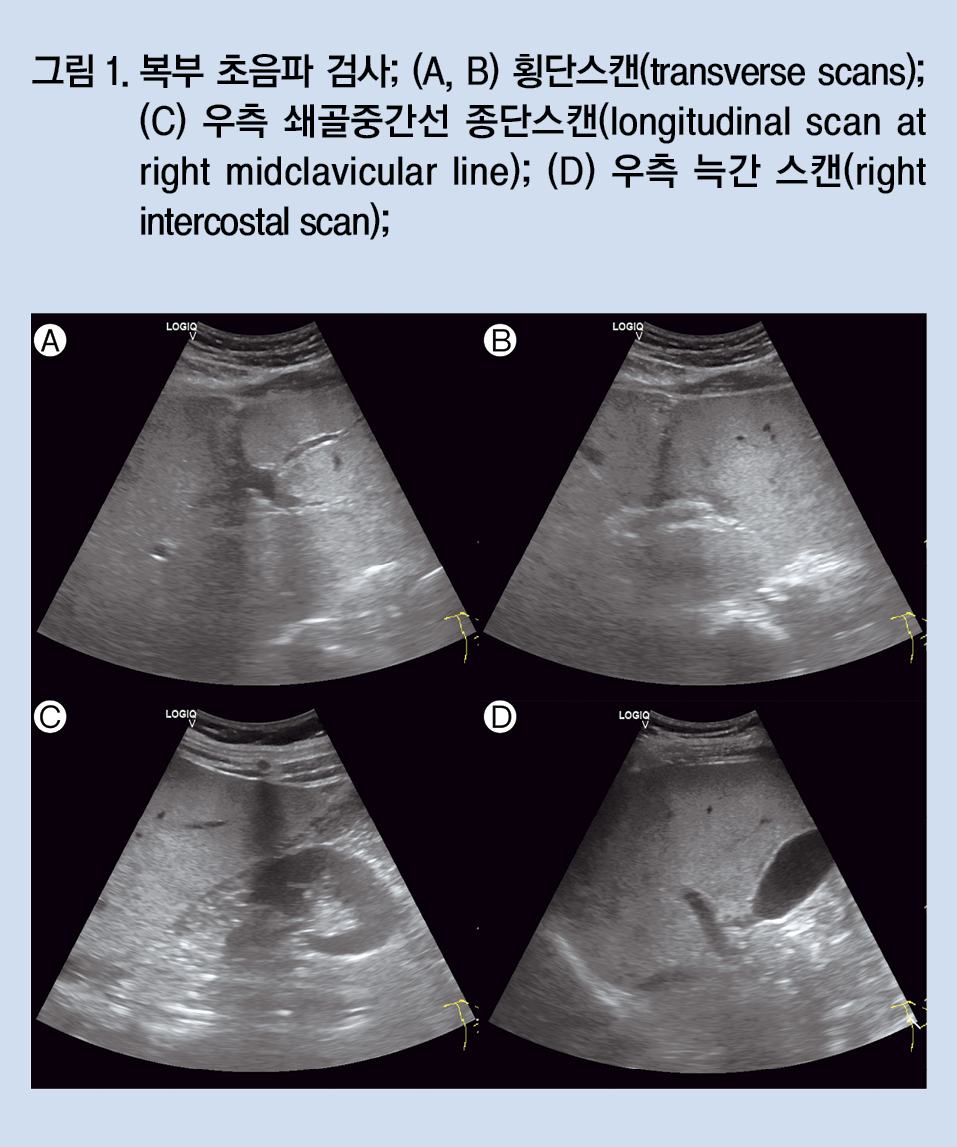

복부 초음파 검사에서는 중등도 이상의 간지방증 소견이 관찰되었다(그림 1).